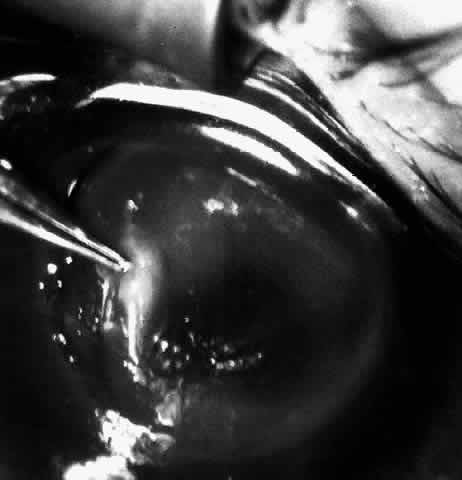

At this point, if intraocular surgery, that is, cataract extraction, pupilloplasty, or membranectomy, is to be done, it is performed through a limbal incision with a vitreous cutting instrument such as the Microvit or Ocutome (Fig. 8). The limbal incision may be closed with 8-0 polyglactin 910 (Vicryl) sutures. After the intraocular procedure is completed and before the epikeratophakia procedure is resumed, it is important to return the eye to normal pressure by injecting balanced salt solution. I prefer to accomplish this with a 30-gauge sharp paracentesis injection through clear cornea.

Fig. 8. After trephination, intraocular surgery may be carried out through a limbal approach if required. Note that the Flieringa ring shown is no longer routinely used.